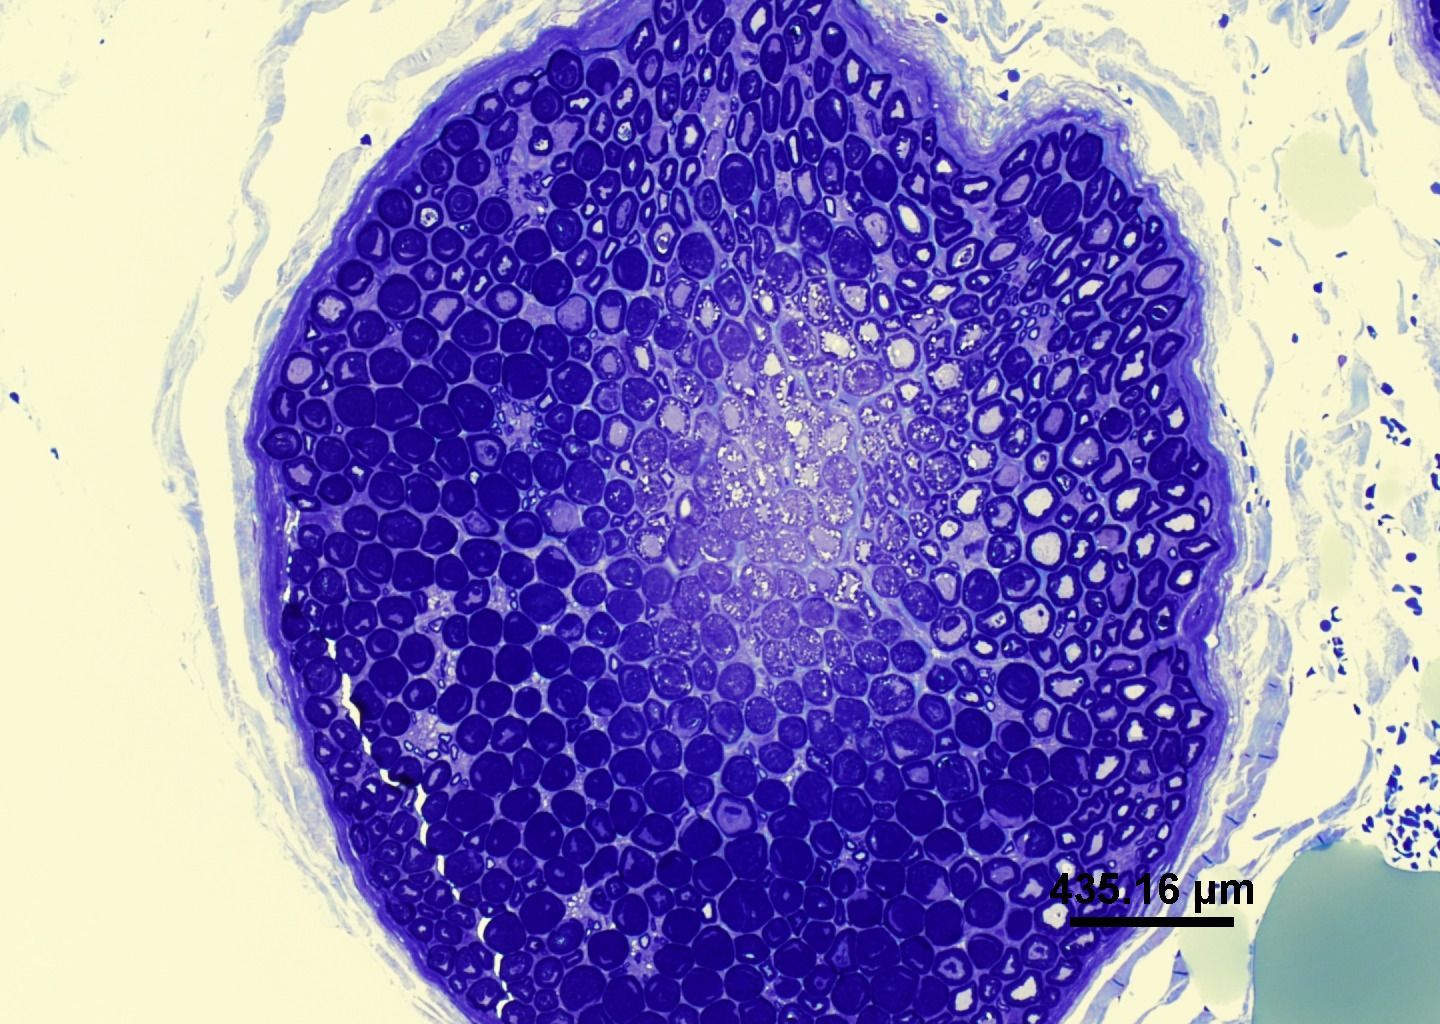

- Demonstracija specifičnih ciljeva krvnih stanica unutar biopsije BMT-a

- Dijagnostički polutanki rezovi smole